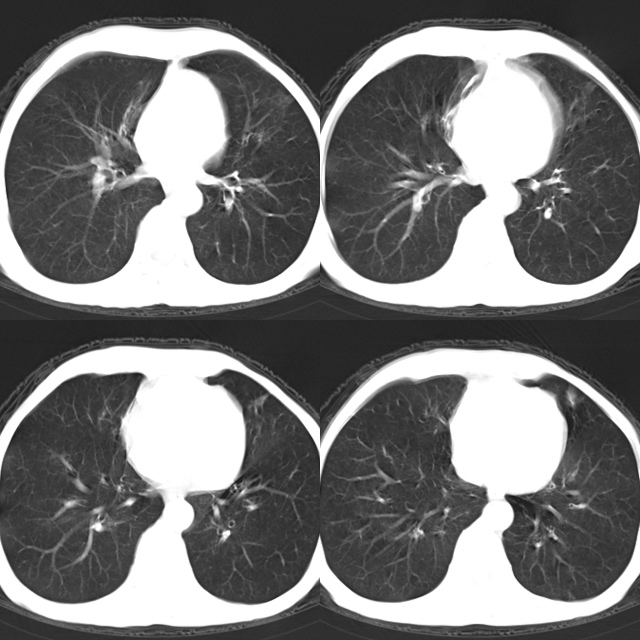

以下是引用心路寻觅在2010-4-17 18:35:00的发言:[br]纵膈多组淋巴结肿大呈“冰冻纵膈”,左肺上叶空洞伴其内结节密度影,考虑淋巴瘤伴左肺上叶曲霉菌感染。[br][br][本贴已被 心路寻觅 于 2010-4-17 18:36:23 修改过]

以下是引用zhangzhongshou在2010-4-17 19:32:00的发言:[br]一元论考虑左肺空洞型肺癌并纵隔淋巴结转移可能性大。